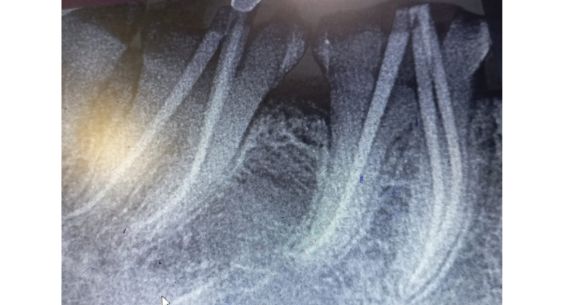

Root Canal Treatment & Various Crowns

Rudra Dental understands that dental health goes beyond appearances. Our comprehensive root canal treatments and diverse crown options are tailored to restore both the health and beauty of your teeth. Root canal treatments, carried out with precision and care, alleviate the discomfort caused by infected or damaged pulp. Our expert team ensures minimal discomfort and swift recovery, revitalizing your oral health.

Root Canal